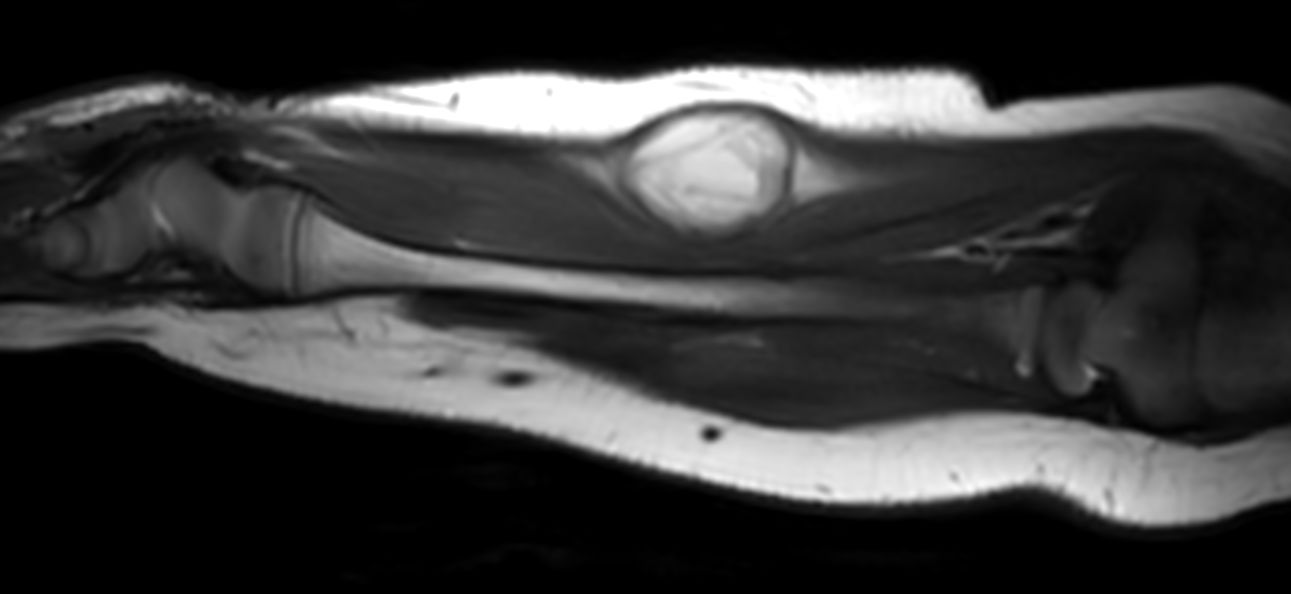

Pediatric forearm with lesion

Pediatric patient with a lesion in the forearm. mDIXON XD provides uniform fat-free imaging and allows for multiple image types in one single scan. Integration of Compressed SENSE acceleration technique enables speeding up of the entire exam.

Coronal T1w TSECompressed SENSE